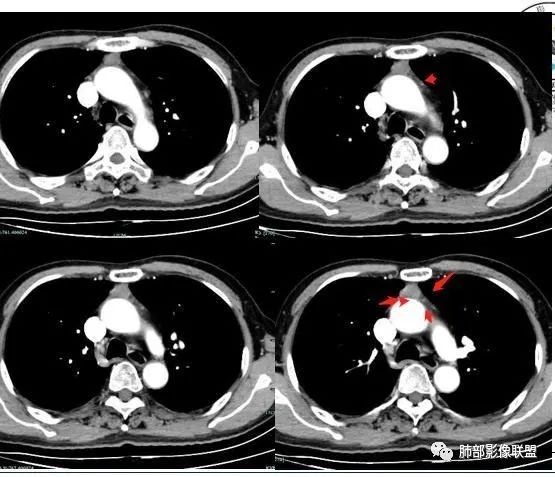

影像基础胸腺瘤的分类分期及ct表现归纳

胸腺瘤基础影像

胸腺上皮性肿瘤最新组织学分型临床分期影像表现